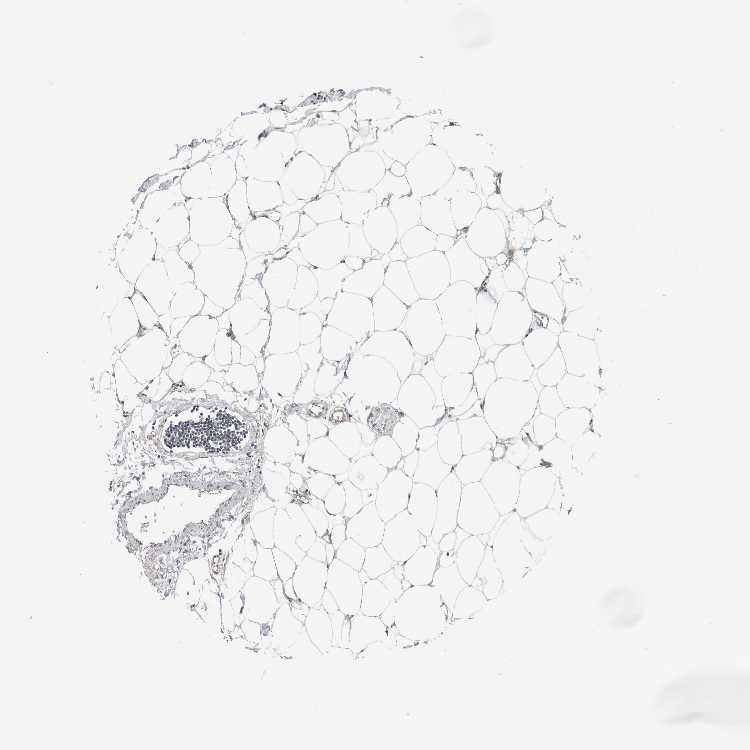

SOFT TISSUE 1 - Antibody stainingi

Antibody staining in the annotated cell types in the current human tissue is reported as not detected, low, medium, or high, based on conventional immunohistochemistry profiling in selected tissues. This score is based on the combination of the staining intensity and fraction of stained cells.

Each image is clickable and will lead to virtual microscopy that enables deeper exploration of all samples and also displays staining intensity scores, fraction scores and subcellular localization as well as patient and tissue information for each sample.

Antibody HPA030419Antibody HPA030420Antibody HPA030422Antibody CAB025196Antibody CAB080286Antibody CAB080287

Chondrocytes Not detectedNot detectedHigh-LowNot detected

Fibroblasts Not detectedNot detectedHighNot detectedNot detectedNot detected

Peripheral nerve --Not detectedNot detectedNot detected-